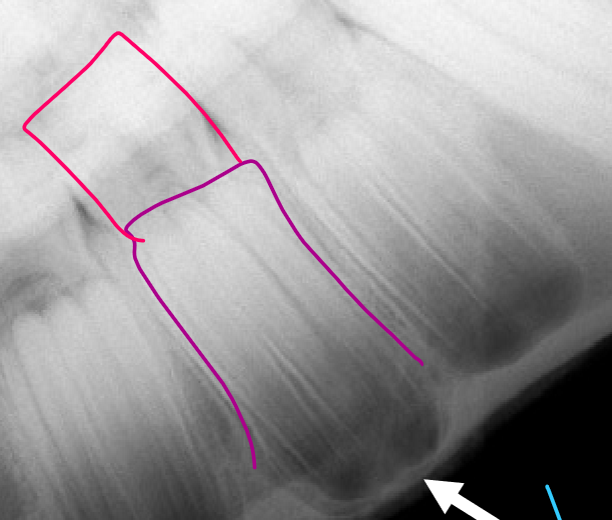

What is the pink structure?

Dental cap/ baby tooth

What is the purple structure?

Adult tooth